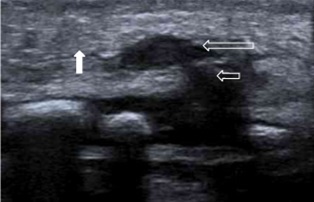

Seguidamente, se realiza ecografía de la lesión (Fig. 2) en la que se aprecia un nódulo hipoecoico de 8 × 4 mm localizado en el tejido celular subcutáneo suprayacente al esternón con comunicación interna con el núcleo de osificación, pero sin destrucción u ocupación de este, asociado a celulitis del tejido celular subcutáneo. Estas imágenes orientan hacia un proceso tumoral benigno sugestivo de SELSTOC.

| Figura 2. Ecografía de partes blandas. Corte longitudinal utilizando sonda lineal de alta frecuencia. Se observa una tumoración ovalada localizada en el tejido celular subcutáneo (flecha larga) de la región preesternal. Dicha tumoración se origina de los núcleos de osificación esternales inferiores (flecha corta). Esta imagen corresponde a la morfología en pesa. También se observa moderada hiperecogenicidad de la grasa subcutánea (flecha rellena) compatible con cambios inflamatorios |